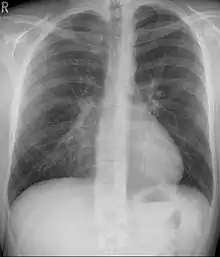

Pectus excavatum is initially suspected from visual examination of the anterior chest. Auscultation of the chest can reveal displaced heart beat and valve prolapse. There can be a heart murmur occurring during systole caused by proximity between the sternum and the pulmonary artery.[15] Lung sounds are usually clear yet diminished due to decreased base lung capacity.[16]

Many scales have been developed to determine the degree of deformity in the chest wall. Most of these are variants on the distance between the sternum and the spine. One such index is the Backer ratio which grades severity of deformity based on the ratio between the diameter of the vertebral body nearest to xiphosternal junction and the distance between the xiphosternal junction and the nearest vertebral body.[17] More recently the Haller index has been used based on CT scan measurements. An index over 3.25 is often defined as severe.[18] The Haller index is the ratio between the horizontal distance of the inside of the ribcage and the shortest distance between the vertebrae and sternum.[19]

Chest x-rays are also useful in the diagnosis. The chest x-ray in pectus excavatum can show an opacity in the right lung area that can be mistaken for an infiltrate (such as that seen with pneumonia).[20] Some studies also suggest that the Haller index can be calculated based on chest x-ray as opposed to CT scanning in individuals who have no limitation in their function.[21]